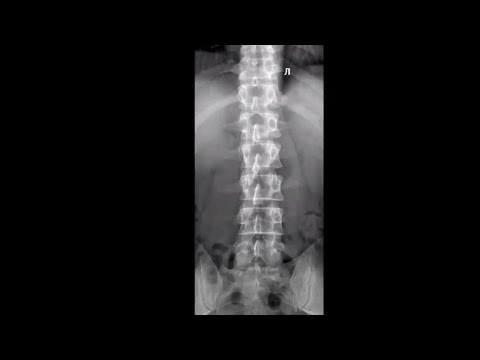

Укладка тазобедренного сустава (Новое)

Видеоурок по позиционированию области исследования для рентгенолаборантов. Остались непонятные моменты? Задавайте свои вопросы под видео, и наши эксперты ответят на них. А может вы уже знаете, какую укладку хотите увидеть следующей? Подписывайтесь на наш канал, нажимайте "колокольчик" рассказывайте о том, что вы хотите изучать и прокачивайте свои навыки. Социальные сети Центра диагностики и телемедицины: Telegram: